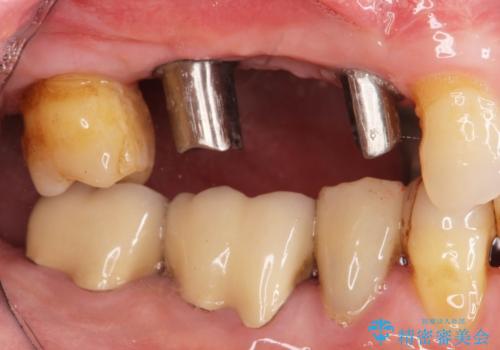

- 右上の奥歯を失ってしまい、「全然モノが噛めない、しっかりと噛めるようになりたい。」

、と入れ歯ではなくインプラント治療を希望され来院されました。

3本の歯が失われた状態を、2本のインプラントで支えるブリッジでの咬合機能回復を計画します。